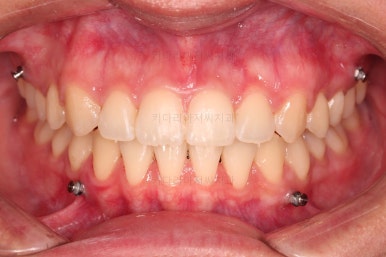

장치를 부착했는데요.

윗니는 웃을 때 더 많이 보이기 때문에 세라믹 장치를 선택하셨고, 아랫니는 거의 안보이는 타입이셔서 메탈장치로 부착을 했습니다.

위아래 둘 다 자가결찰 장치였고요.

동일 회사의 장치였으며 단지 재질만 메탈이냐 세라믹이냐의 차이가 있었던거죠.

이렇게 위아래는 설측이든 뭐든 메탈이든 세라믹이든 마음대로 섞을 수 있습니다.

그래서 위아래 좌우 모두 다른 용도로 미니스크류가 식립되었고요.

윗니의 배열과 위치는 거의 완성이 되었고요.

아래는 아직 틈이 많이 보이죠.

아랫니 틈은 거의 없어졌네요.

교합 양호하고 치아 사이 틈새도 잘 모아졌습니다.

이제 부산치아교정 전후 비교를 해볼게요.

틈새가 예쁘게 모아졌고요.

교합도 좋아졌고, 앞니도 가지런해졌네요.